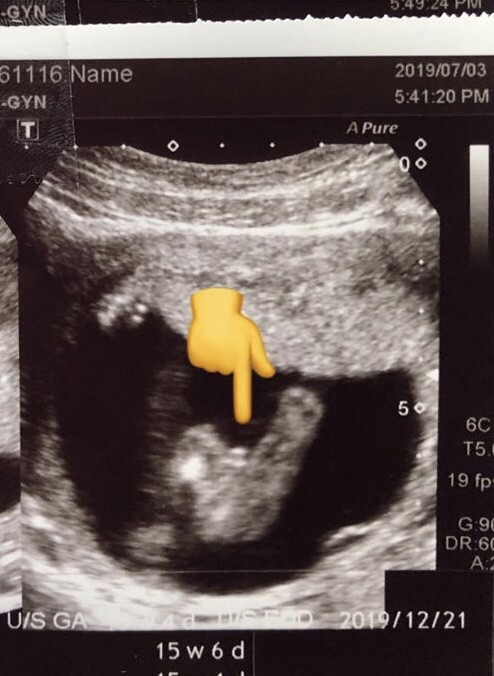

แบบนี้ ผญ หรือ ผช คะ

หมอบอกผู้ชายค่ะ